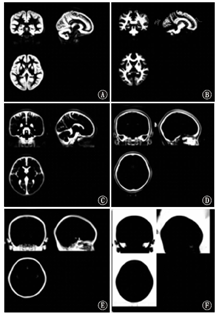

数据均使用SPM8(http://www.fil.ion.ucl.ac.uk/spm/software/spm8/)、VBM8工具箱(http://dbm.seato.uni-jena.de/vbm8/)进行处理。(1)组织分割:使用自定义的Dartel脑分割模板(图1),对入组及2年后随访时的所有被试者的原始T1加权像图像进行分割处理,得到蒙特利尔神经学研究所(MNI)标准空间下各被试灰质和其他组织的图像及原始空间下各被试灰质、白质和脑脊液的图像。(2)平滑处理:用8 mm半高全宽高斯核平滑对脑白质体积图进行平滑。(3)脑白质体积的提取:选取FSL(https://fsl.fmrib.ox.ac.uk/fsl/fslwiki/)软件中自带的脑叶模板MNI-maxprob-thr0-1mm.nii,依次提取各脑叶,使用ANTS(http://picsl.upenn.edu/software/ants/)软件进行配准,制作自定义的脑叶模板(图2),分别提取每个被试者的额叶、颞叶、顶叶、枕叶、左右大脑半球的白质体积及全脑体积。

注:A:灰质;B:白质;C:脑脊液;D:背景1;E:背景2;F:背景3 A: gray matter;B:white matter;C:cerebrospinal fluid;D:background 1;E:background 2;F:background 3